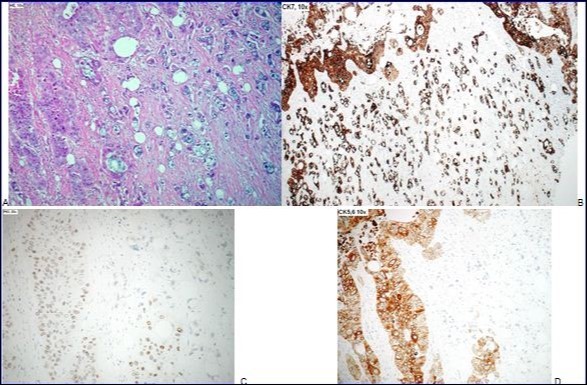

Microscopically, the tumor proliferation consisted mainly of islands and nests with a squamous differentiation, composed of large cells with slightly abundant eosinophilic cytoplasm and enlarged pleomorphic nuclei, with irregular contours, coarse chromatin and prominent nucleolus. There was presence of some mitotic figures, dyskeratotic cells and foci of keratinization. Focally, there was formation of small glandular structures with some isolated cells with vacuolated cytoplasm and showing mucus secretion. Immunohistochemical analysis showed a weak nuclear positivity for P63 in the squamous portion of the lesion with obvious negativity of adenocarcinomatous cells. Cytokeratin 5/6 also showed a clear membrane and cytoplasm positivity in the squamous component, the adenocarcinoma component remaining negative. Cytokeratin 7 was positive in both components and cytokeratin 20 showed few positive cells (Figure 4: A, B, C, D). Among 32 regional lymph nodes examined, there were four lymph nodes with metastasis. The TNM classification (according to the seventh edition UICC 2009) was therefore pT4b pN2 (4/32) V1 L1 Pn1.

Figure 4.A-95% of tumor is a poorly differentiated squamous carcinoma with rare foci of keratinisation, and <5% of tumor is a poorly differentiated adenocarcinoma, with some isolated cells. B-Both components, squamous carcinoma and adenocarcinoma, are Cytokeratine 7 positive. C- Squamous component shows a nuclear positivity for P63, with negativity of the adenocarcinoma. D-Cytokeratine 5, 6 is positive in the squamous component, but not in the adenocarcinomatous component.